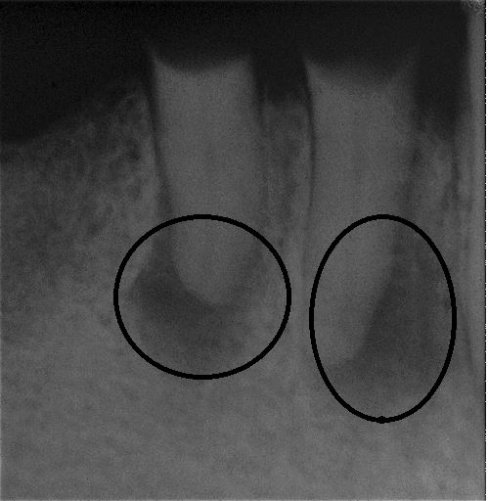

Fallbeispiel für eine große Entzündung an der Wurzel

Wurzel nach erfolgreicher Behandlung 2 Monate später schon fast ausgeheilt

Auch bei einer befriedigenden Wurzelfüllung kann der Erfolg versagt bleiben. Ursachen für Misserfolge sind z. B. wenn zuvor aufgrund einer komplexen Kanalanatomie die Reinigungswirkung zu gering war und dadurch die Kanäle nicht ausreichend von Bakterien befreit werden konnten. In solchen Fällen kann es gelingen, den Zahn durch eine kompromisslose Revision (Wiederholung) der Wurzelkanalbehandlung zu erhalten.